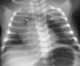

Vibrator chest physiotherapy in neonates

Postural drainage (PD) is the drainage of lung secretions using gravity. It is used to treat a variety of conditions that cause the build-up of secretions in the lungs. [Source: Wikipedia ]